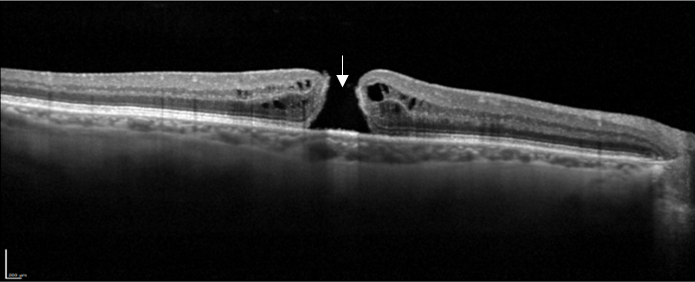

Des rétinophotos couleurs permettent de visualiser la veine concernée par l’occlusion, la présence d’hémorragies intra rétiniennes, de nodules cotonneux etc … L’OCT objective la présence d’un œdème maculaire et de mesurer son épaisseur. Enfin c’est l’angiographie à la fluorescéine qui nous renseigne sur l’état de la circulation du sang dans les vaisseaux rétiniens et la présence de complications ischémiques périphériques.

Coupe OCT maculaire montrant un œdème maculaire cystoïde post OBVR inférieure.

• Tomographie par Cohérence Optique (OCT) : Permet d'évaluer le degré de gonflement rétinien (œdème maculaire), la complication la plus fréquente et principale cause de la baisse de vision.